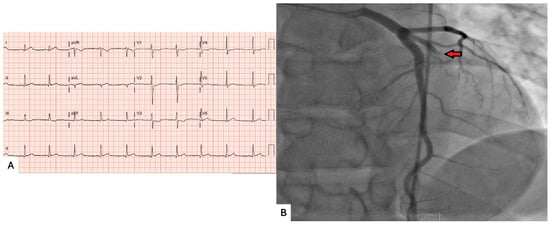

We describe the case of a 26-year-old man who presented with acute chest pain and was found to have single-vessel coronary occlusion most consistent with probable paradoxical embolism. Coronary angiography demonstrated complete occlusion of the ramus intermedius artery. Aspiration thrombectomy restored flow without

We describe the case of a 26-year-old man who presented with acute chest pain and was found to have single-vessel coronary occlusion most consistent with probable paradoxical embolism. Coronary angiography demonstrated complete occlusion of the ramus intermedius artery. Aspiration thrombectomy restored flow without stent implantation. Intravascular ultrasound showed no plaque rupture, atherosclerosis, or coronary dissection, supporting but not definitively confirming an embolic etiology. Transthoracic and transesophageal echocardiography subsequently identified a large patent foramen ovale with bidirectional shunting. Lower-extremity Doppler studies and an extensive hypercoagulable evaluation were negative. The patient later underwent successful percutaneous closure of the patent foramen ovale. This case highlights probable paradoxical coronary embolism as a rare cause of acute myocardial infarction in a young patient without significant atherosclerotic disease and underscores the value of multimodality imaging in supporting the diagnosis and guiding management.